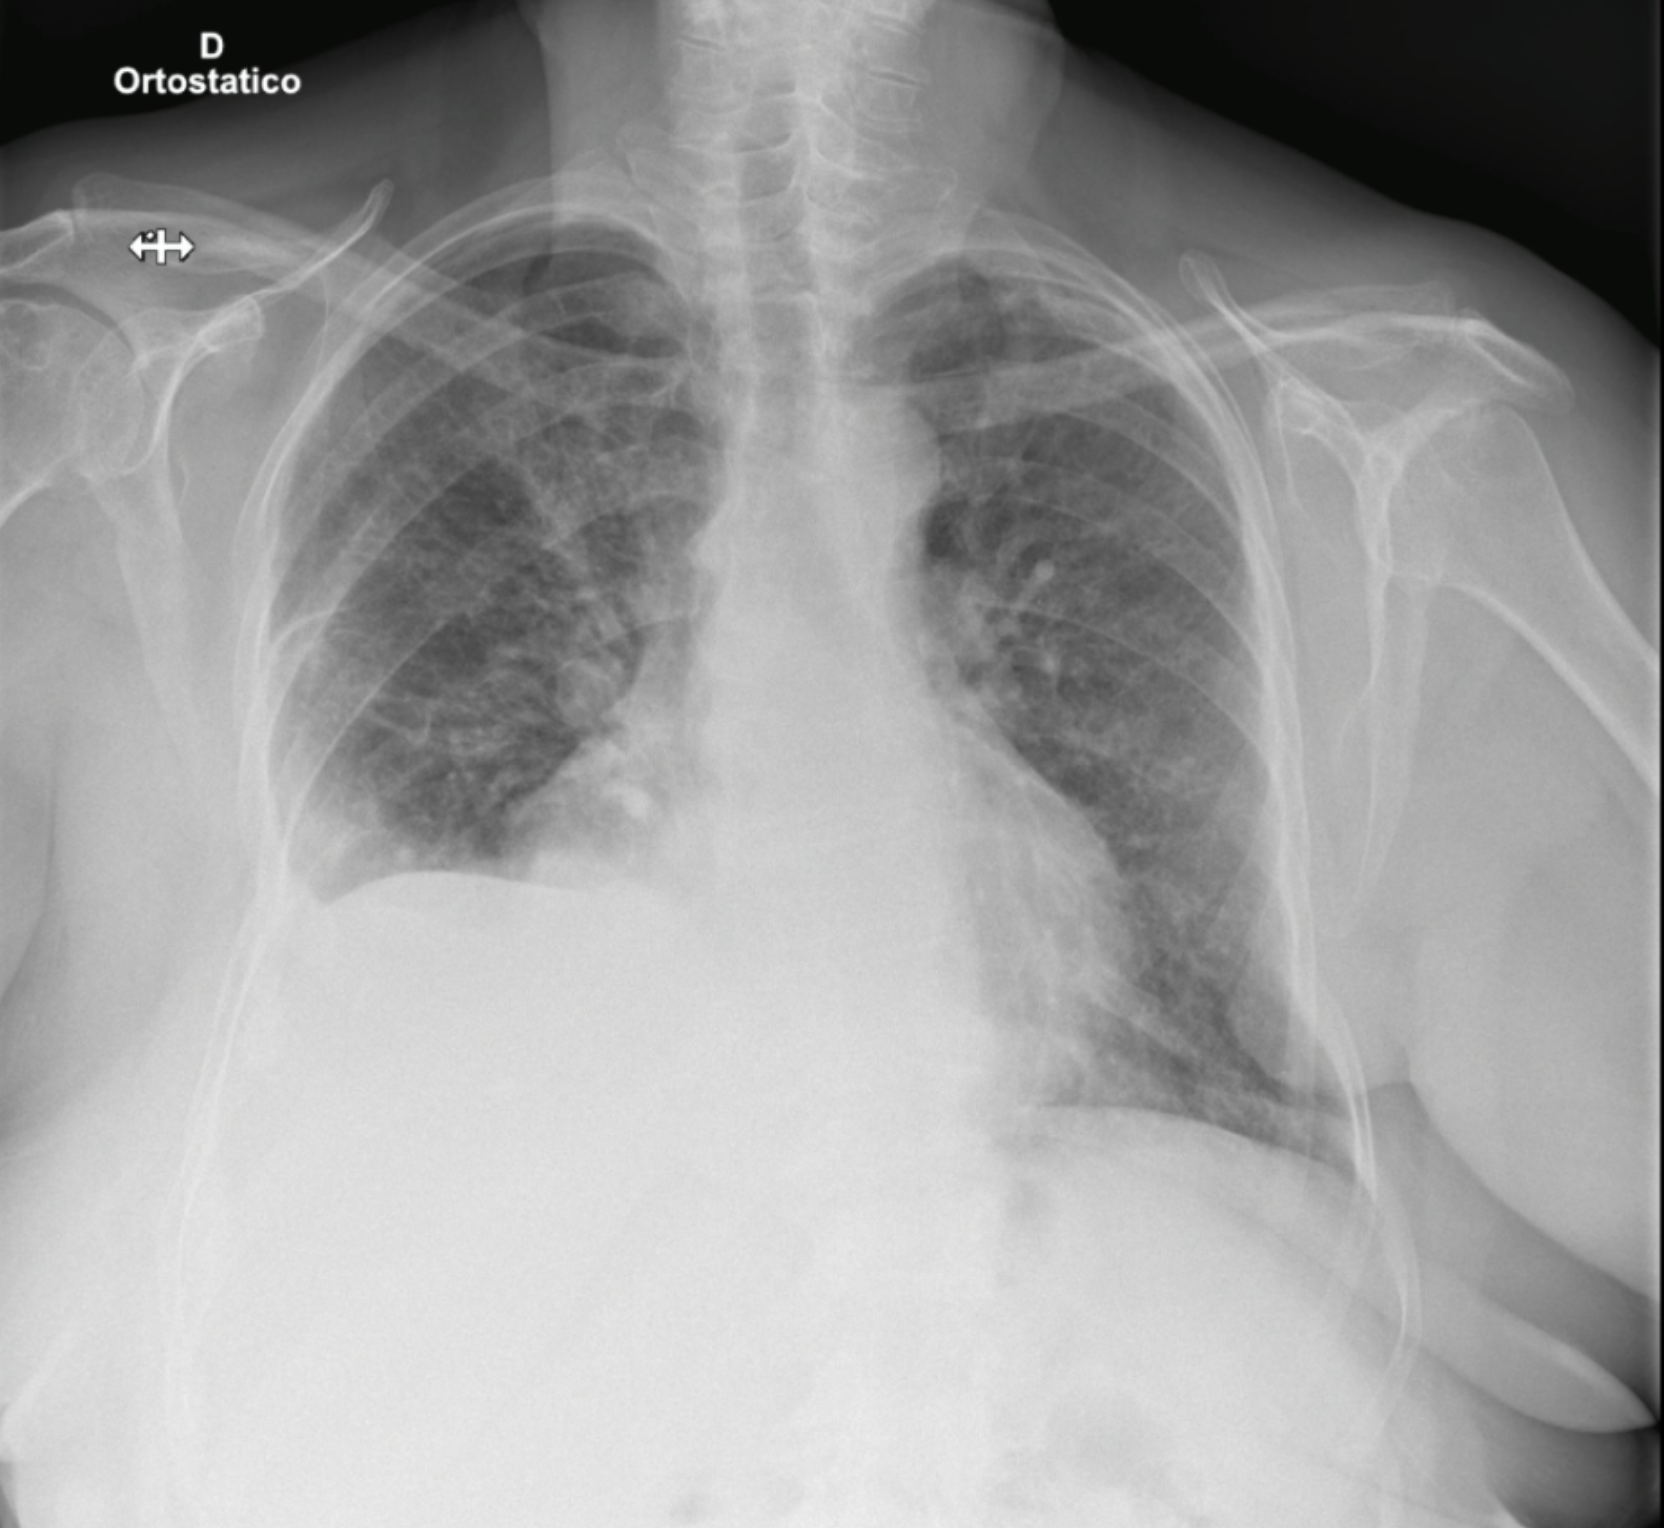

torax_derramepleural

Observa-se derrame pleural à direita, associado a velamento basal e provável atelectasia compressiva. Nota-se também aumento difuso da trama pulmonar com padrão interstício-alveolar bilateral, de predomínio perihilar, sugestivo de congestão pulmonar. Conjunto de achados compatível com edema pulmonar de provável etiologia cardiogênica.